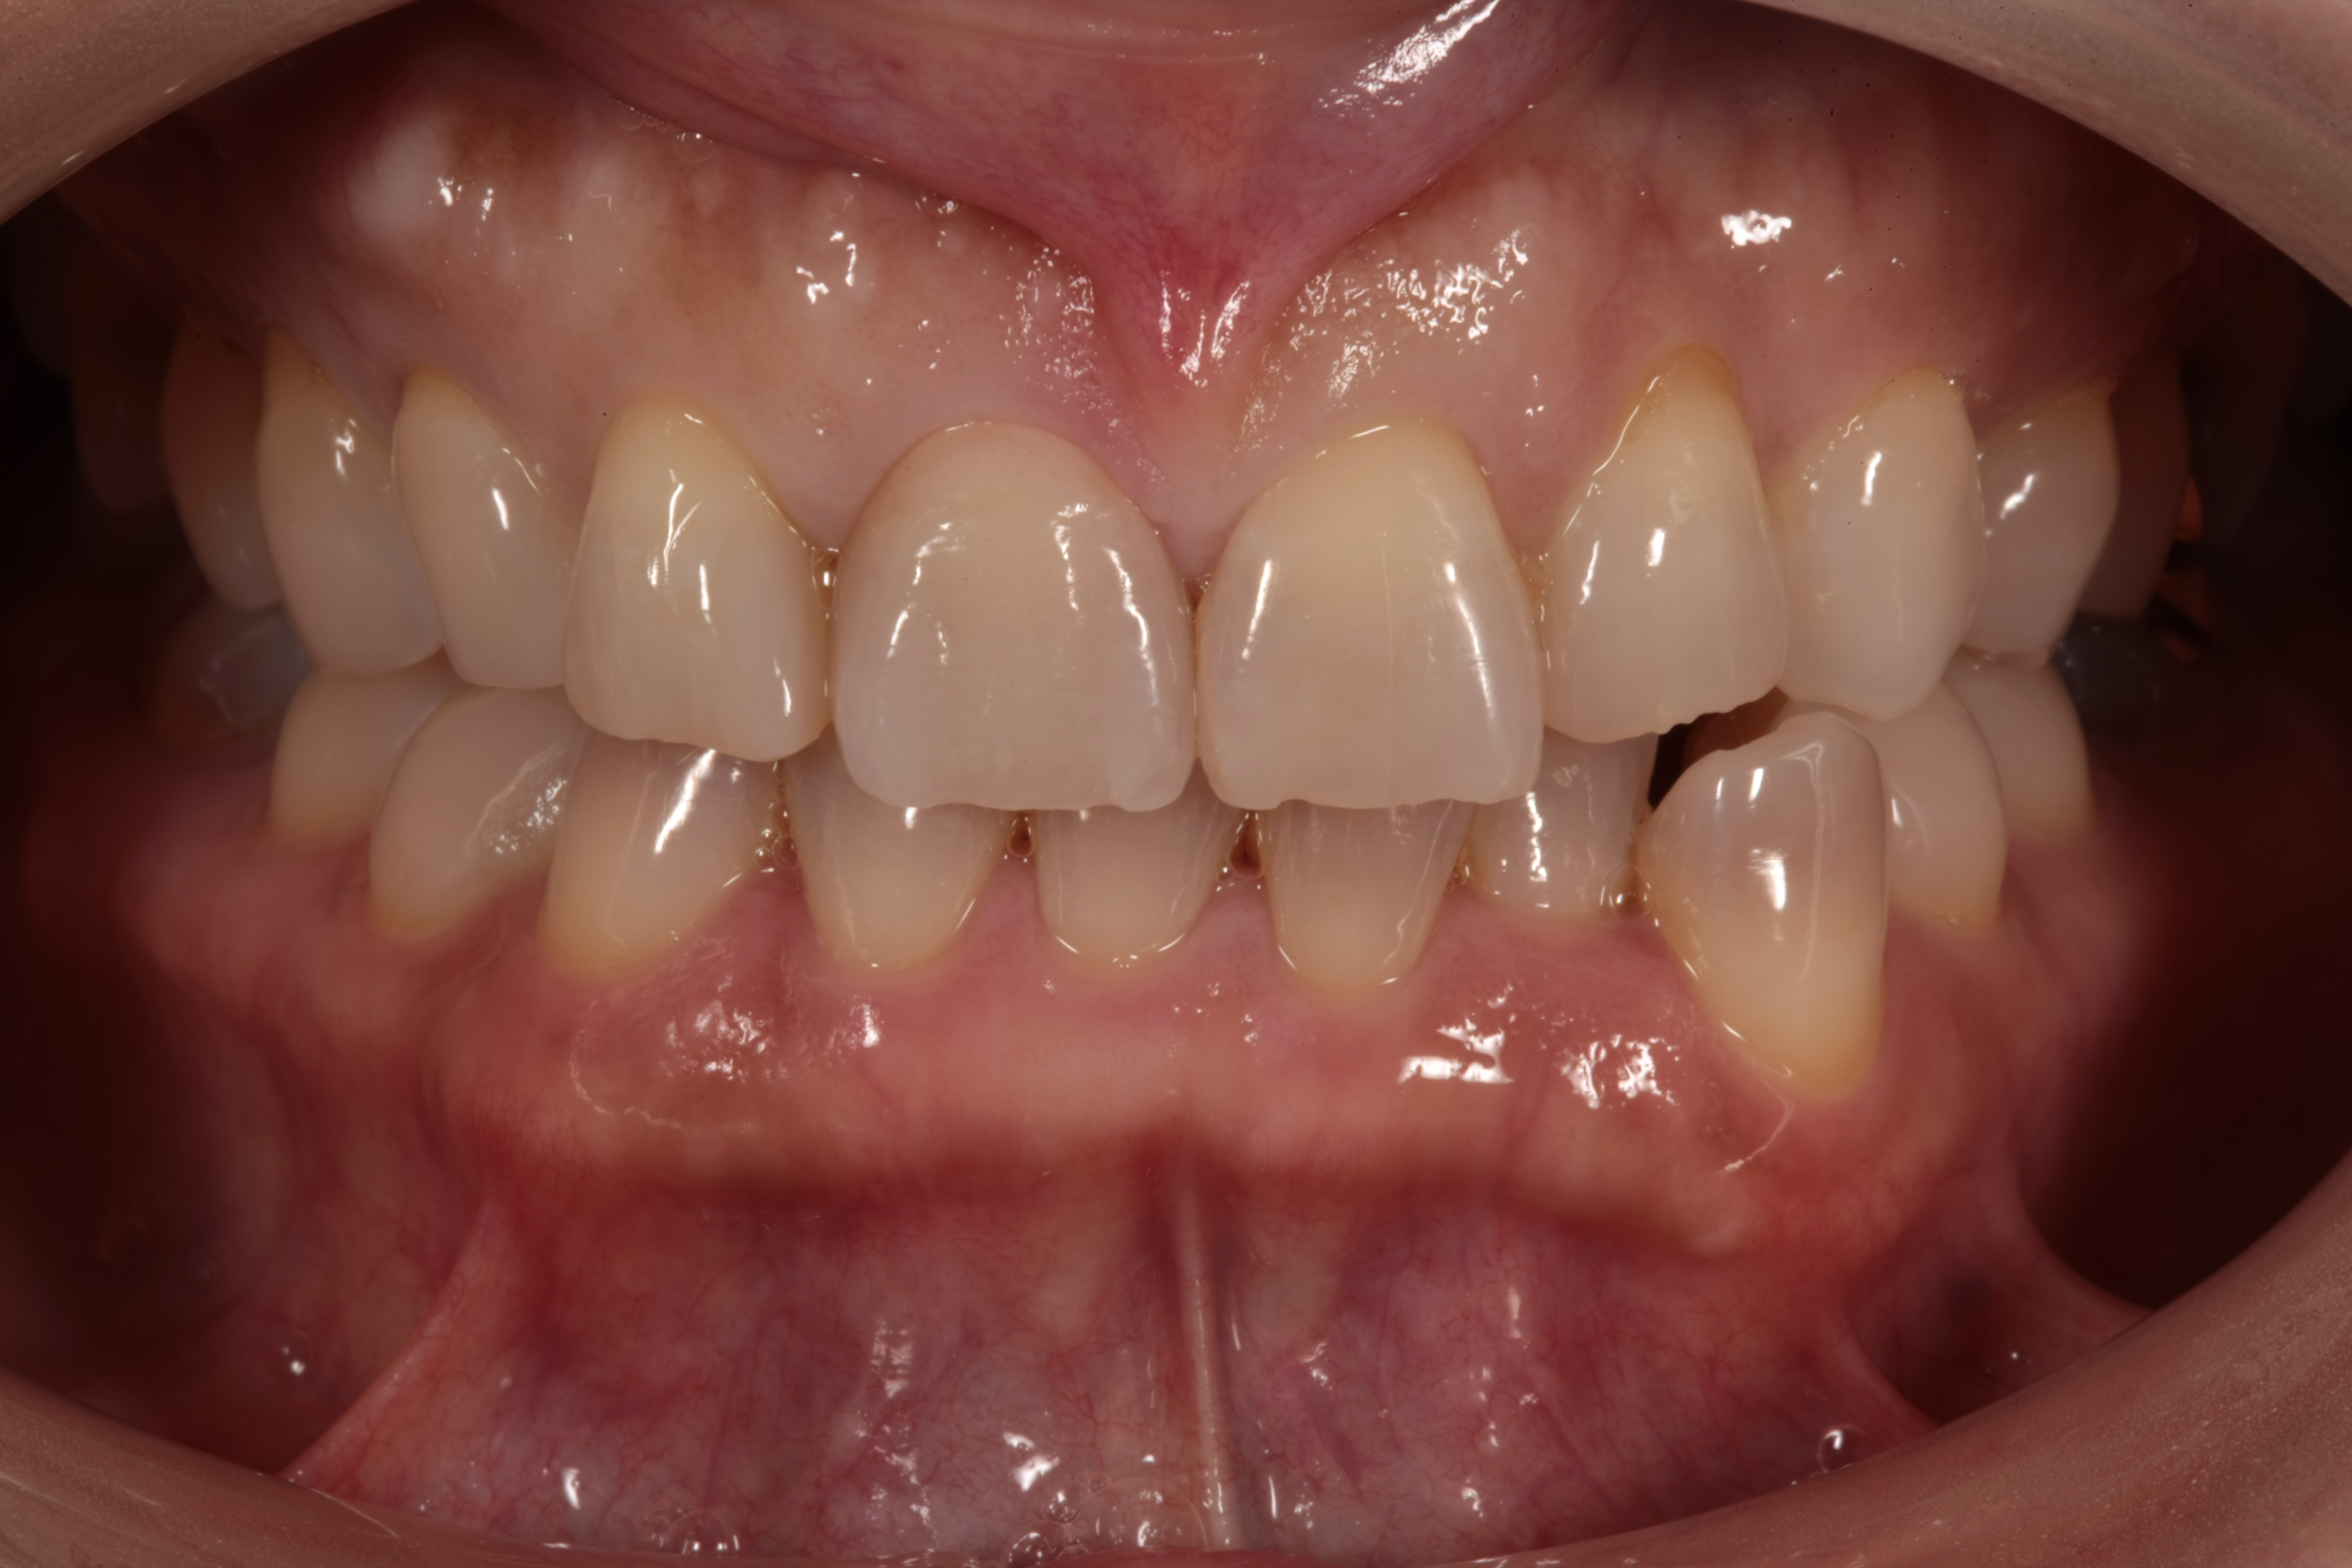

お口の中を見てみると

このような状態でした。

どこが差し歯かわかりますよね?

矢印のこちらの歯です。

歯の根元が黒くなり、

歯の色が合わなく1本だけ浮いて見えます。

また歯の形も膨らみが強く、いかにも「作った歯」という感じです。

今回の患者さんは、テトラサイクリン歯といって元々、色の濃淡がある歯のグラデーションをしています。よく見ると上の歯と下の前歯の色が違います。

このように特徴があるグラデーションを合わせていくのは技術的に難しくなります。